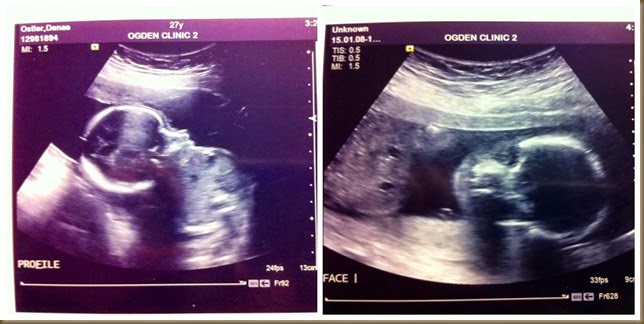

We have a confirmed little BOY on the way folks, and he is very proud of his little manhood. The best news? He is healthy and growing beautifully with no complications! YAY!!! There has been such a weight lifted off of my shoulders since finding that out. I have been one worried and anxious Momma. Not that I would change anything about our perfect little Jayden, but I am glad that our Tristan will have it a little bit easier. :) We cannot wait to meet you and hold you Tristan David Ostler!!! We LOVE you!!!!!

baby220weeks

Just look at that precious little boy all snuggled up, and that face! SO precious!